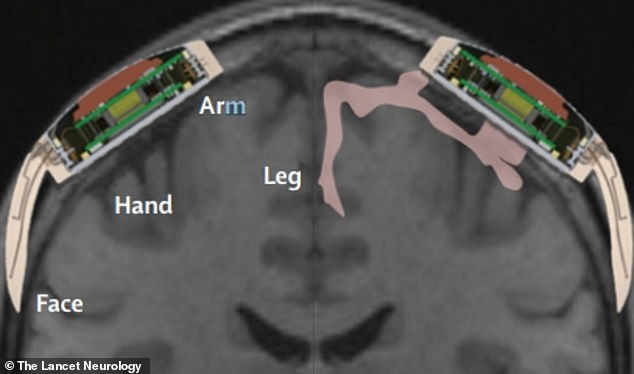

ក្រុមអ្នកស្រាវជ្រាវមកពីសាកលវិទ្យាល័យ Grenoble ក្នុងប្រទេសបារាំង, មជ្ឈមណ្ឌលស្រាវជ្រាវជីវសាស្រ្ត Clinatec និងមជ្ឈមណ្ឌលស្រាវជ្រាវ CEA បានផ្សាំឧបករណ៍ថតសំឡេងនៅផ្នែកម្ខាងនៃក្បាលរបស់លោក Thibault នៅចន្លោះខួរក្បាល និងស្បែក ដើម្បីលាតសន្ធឹងឧបករណ៍ចាប់សញ្ញាតំបន់ខួរក្បាល (sensorimotor cortex) ដែលជាតំបន់បញ្ជាចលនាដៃជើង និងអារម្មណ៍របស់មនុស្ស។ អេឡិចត្រូដប្រមូលសញ្ញាខួរក្បាលរបស់បុរសនោះ ហើយបកប្រែវាឱ្យរ៉ូបូតអាចយល់នឹងធ្វើចលនាតាម៕